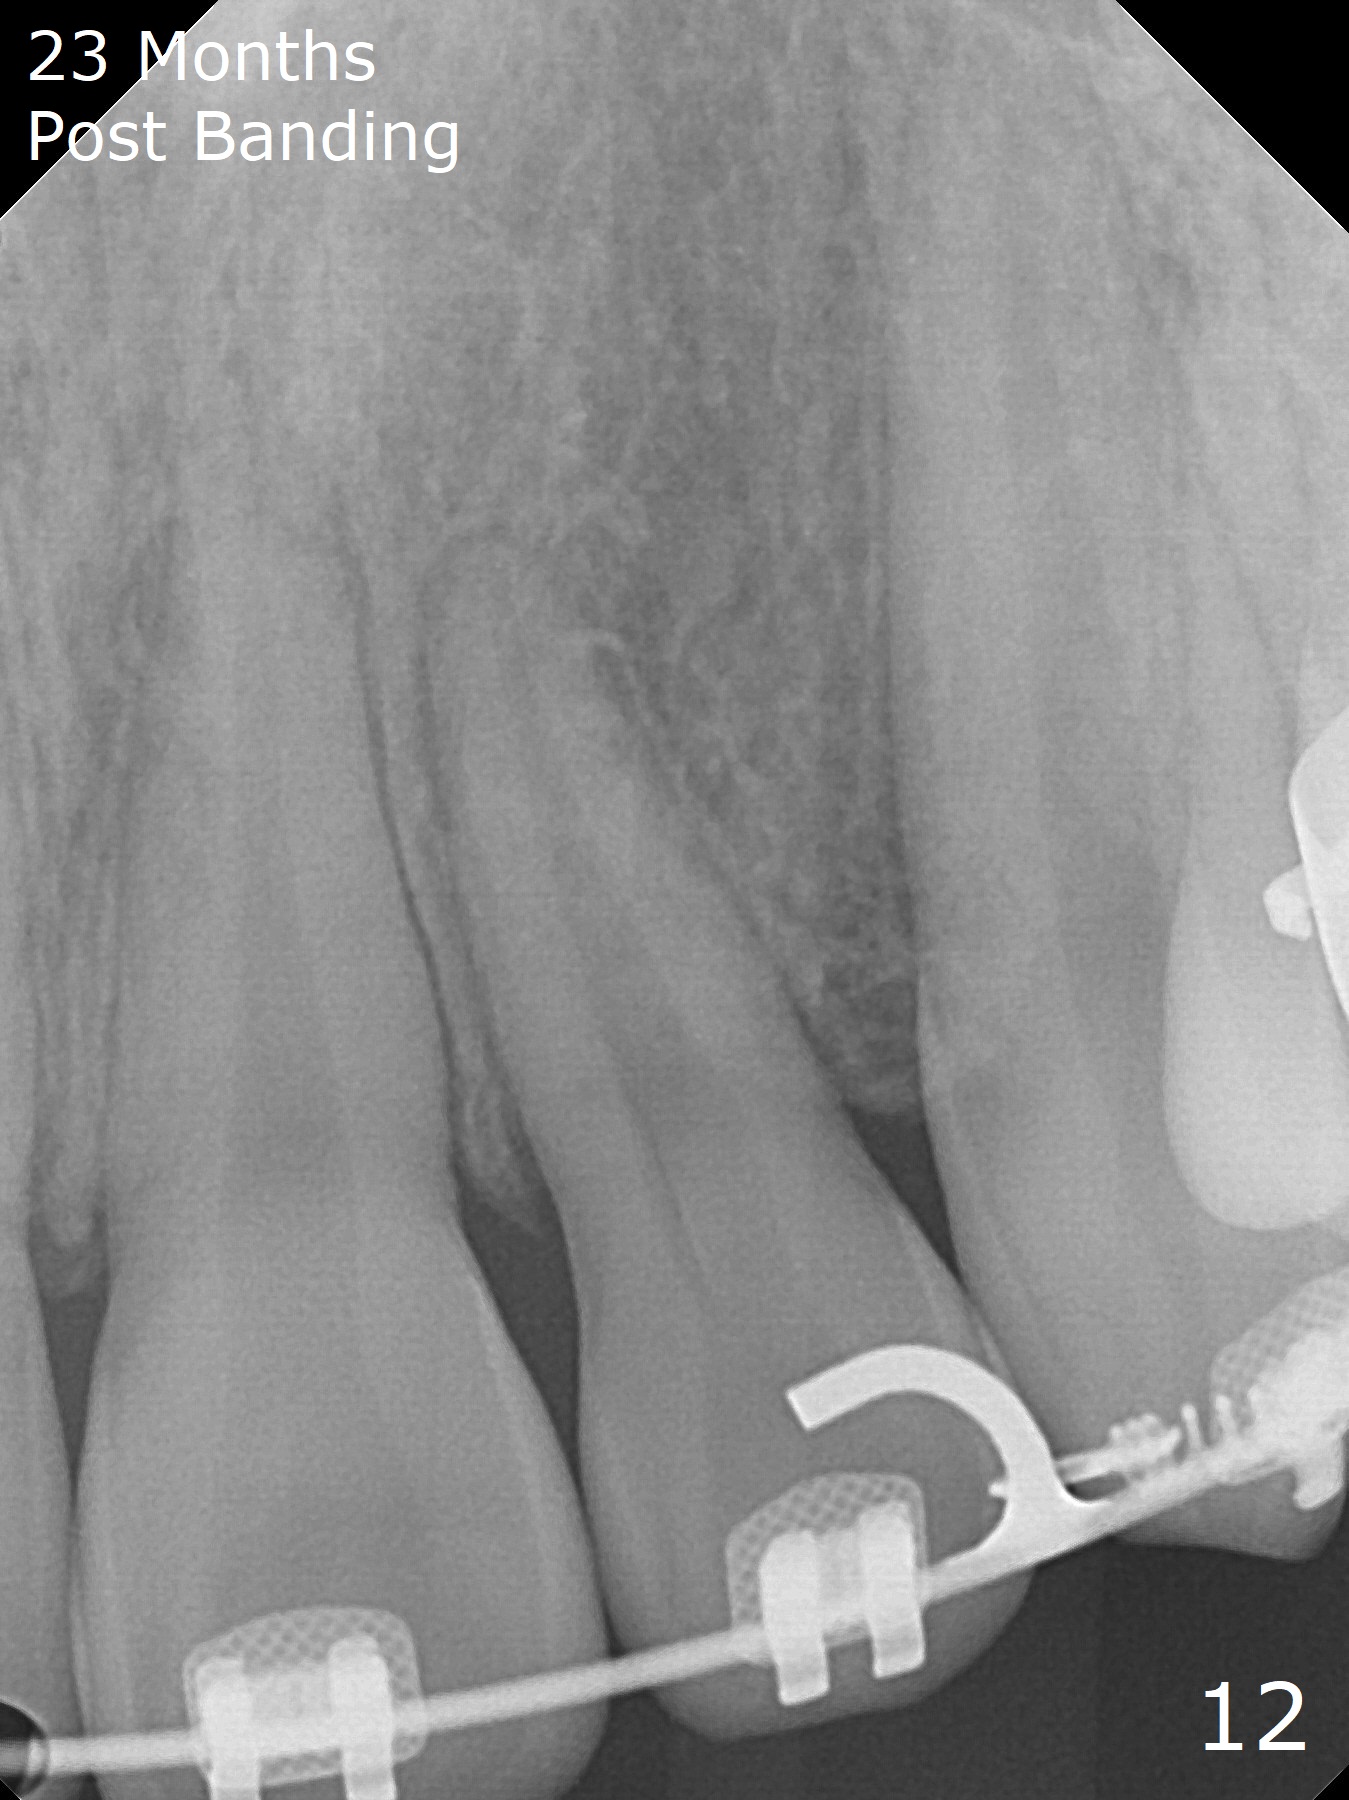

Anterior overbite and overjet and posterior interdigitation are satisfactory, while the roots of the upper incisors look shortened 23 months post banding (Fig.11,12, as compared to pre-banding (Fig.13). Brackets and bands are removed.